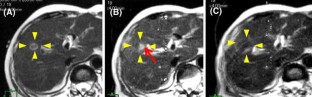

We performed percutaneous ablation therapy for 51 nodules of liver cancer in 34 patients using a navigation system based on open MRI. During the ablation therapy, the ultrasonography (US) probe, needle, and tumor were displayed on the MR image. Immediately after the procedure, the therapeutic effect was evaluated by open MRI.

In all cases, percutaneous puncture into the tumors was successful, even in the case of tumor undetectable by US. Mean fiducial registration error was approximately 3 mm. MR images captured after the procedure clearly demonstrated the ablated area. No mortality or major complications occurred, except for mild hemorrhage, pyrexia, and ascites.